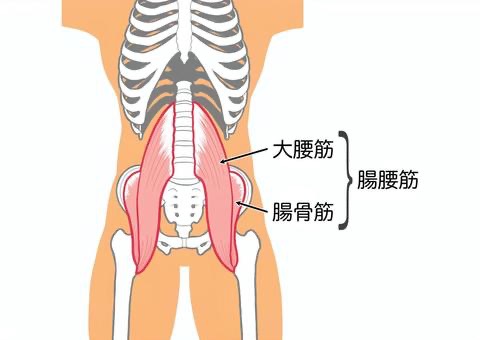

ふくらはぎと太ももの前、腸腰筋(ちょうようきん)のストレッチ

腸腰筋(ちょうようきん)とはあまり聞きなれない筋肉の名前だと思います。腸腰筋は、主に「大腰筋(だいようきん)」と「腸骨筋(ちょうこつきん)」という2つの筋肉から構成される総称です。

これらの筋肉は、お腹の深部、つまり体の中心に近い場所に位置しています。具体的には、背骨の腰の部分(腰椎)から始まり、骨盤の内側を通って、太ももの骨(大腿骨)の付け根に付着しています。

体の奥深くにあるため、直接触って位置を確認するのは難しい筋肉です。しかし、私たちの日常生活における基本的な動作に深く関わっているため、その存在と働きを理解することは非常に重要です。体の表面から見えにくい場所にあるからこそ、意識的にケアをすることが求められます。

腸腰筋のストレッチは、片膝立ちになり股関節前面あたりを伸ばすことで、ストレッチできます。またこのストレッチを行うことにより骨盤前傾の緩和も期待できます。